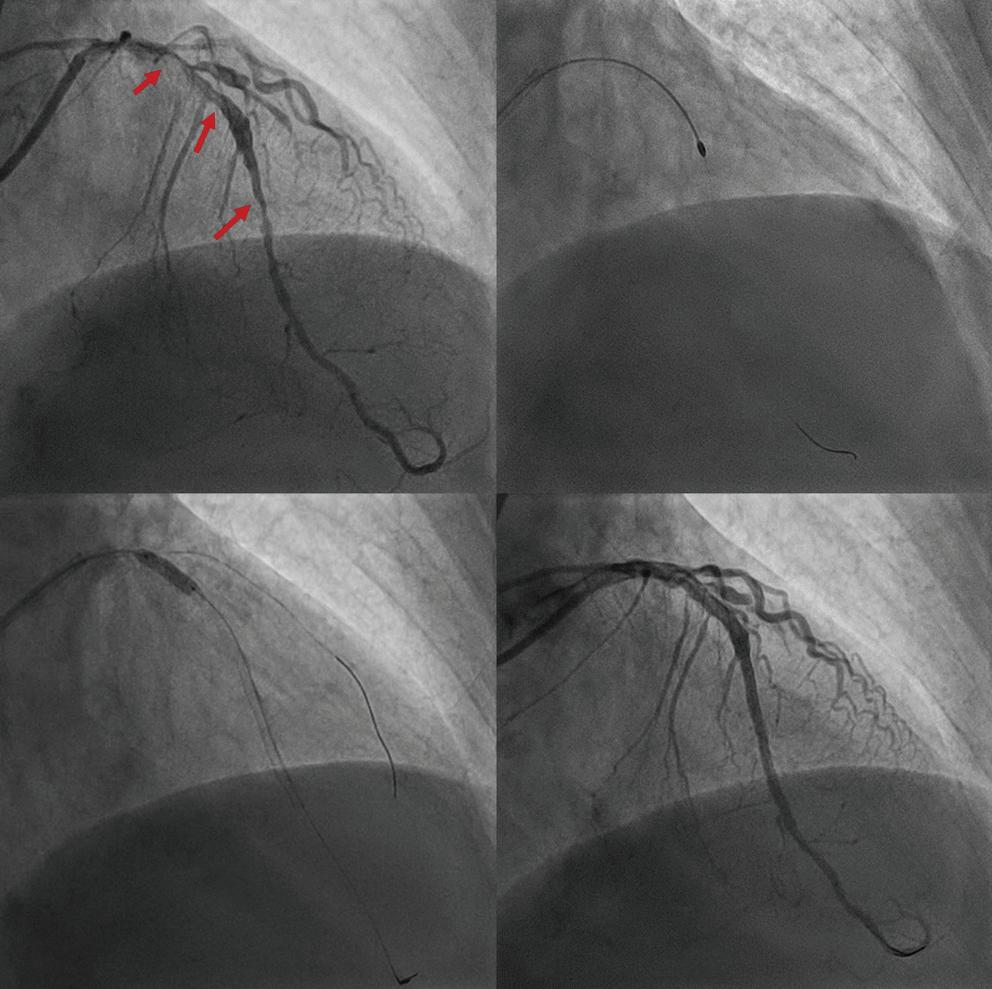

Figure 3: Transsepetal Puncture for Balloon Mitral Valvotomy and Electrophysiology Study in One Go A: Septal puncture using fluoroscopy and transesophageal echocardiography guidance. B: A 23–26 mm Accura balloon was inflated to 26 mm in the right anterior oblique view. Electrophysiological study using one quadripolar catheter for right ventricle pacing and one decapolar catheter in the coronary sinus.